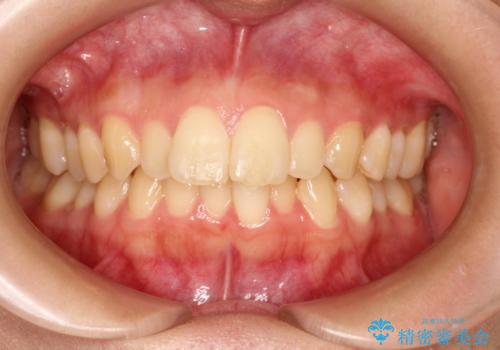

出ている前歯をインビザラインにて引っ込める

- 前歯が少し前に出ているのが気になるとのことで来院されました。

インビザラインにて上顎の歯を全体的に後方に移動させて前歯を引っ込める計画としました。

使用時間を守っていただけたので、比較的スムーズに矯正を終了することができました。